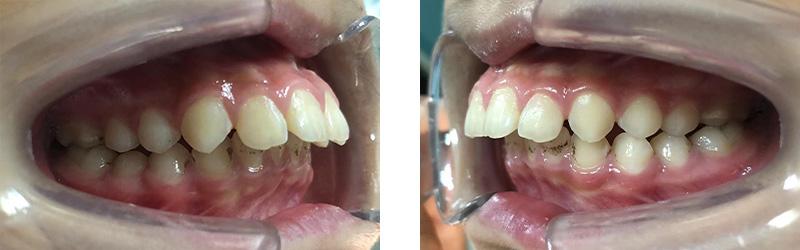

病例分享